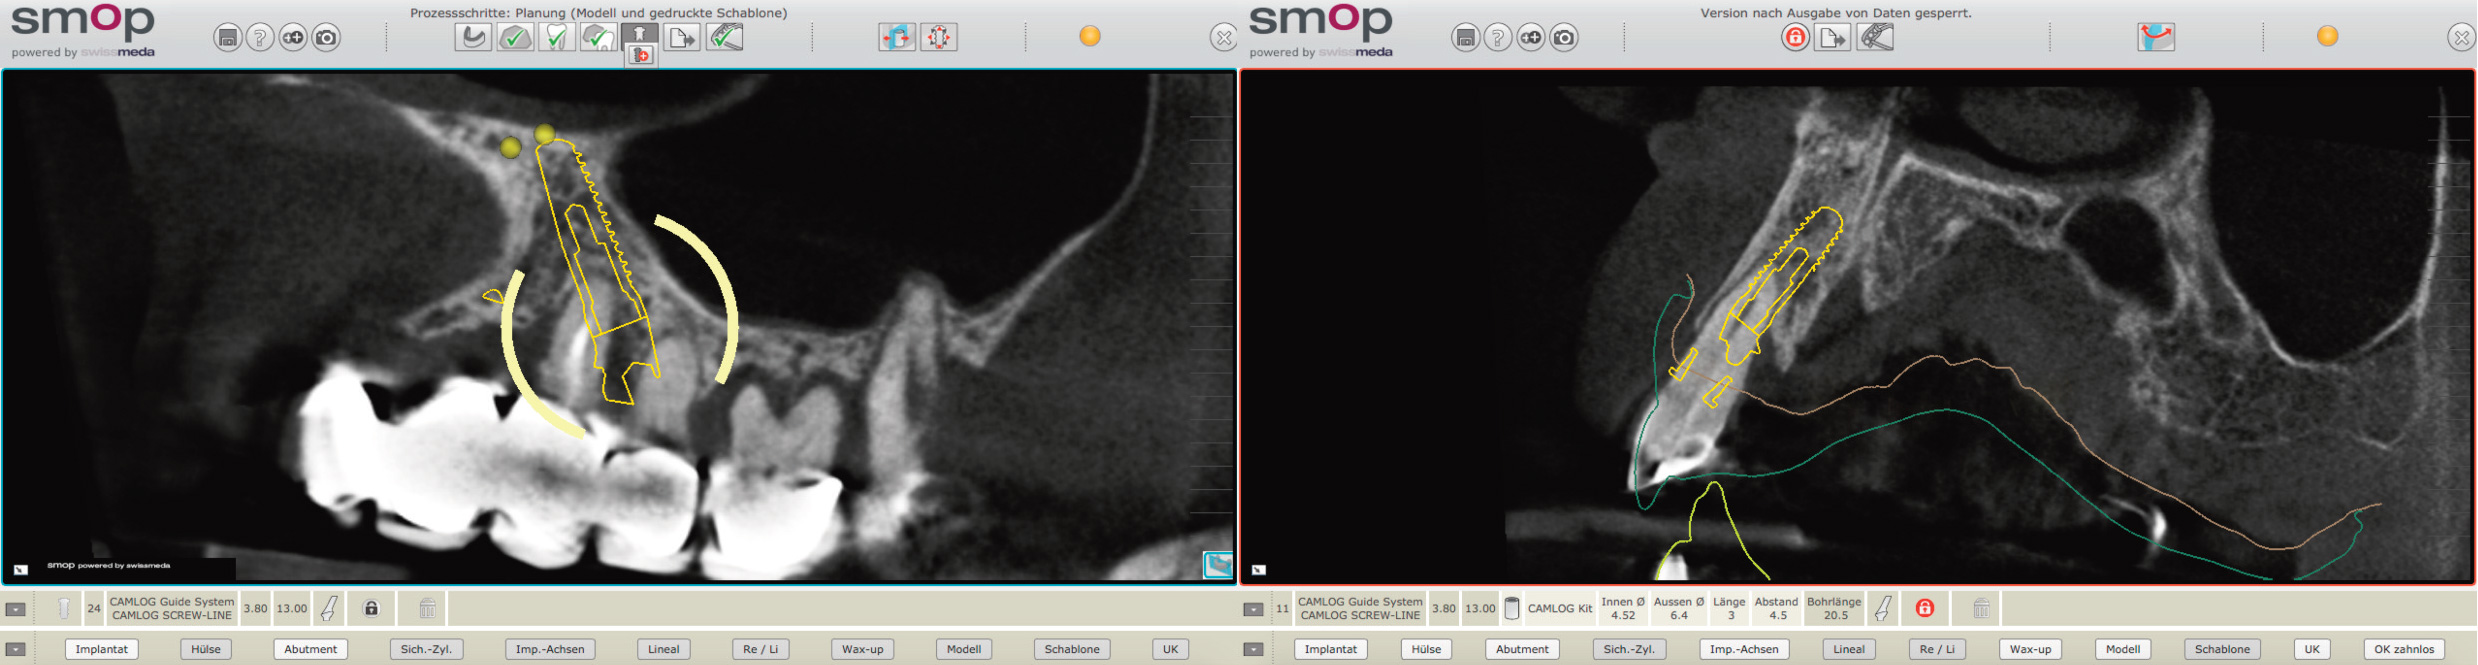

Über die 3D Röntgenaufnahme erhält der Implantologe ein genaues Bild über das vorhandene Knochenangebot.

Dies ermöglicht das exakte Positionieren der notwendigen Implantate. Durch das Hinzufügen der idealen Zahnaufstellung kann diese Position korrekt der Versorgung angepasst werden.

Im ersten Schritt werden die Implantate in der Software ausgewählt und unter Berücksichtigung des Knochenangebotes

in die ideale Position gebracht.

Beim Ausrichten der Implantate werden auch die künftigen Zahnpositionen berücksichtigt.

Damit die Implantate auch exakt an der ausgewählten Position stehen, wird im zweiten Schritt eine Bohrschablone erstellt.